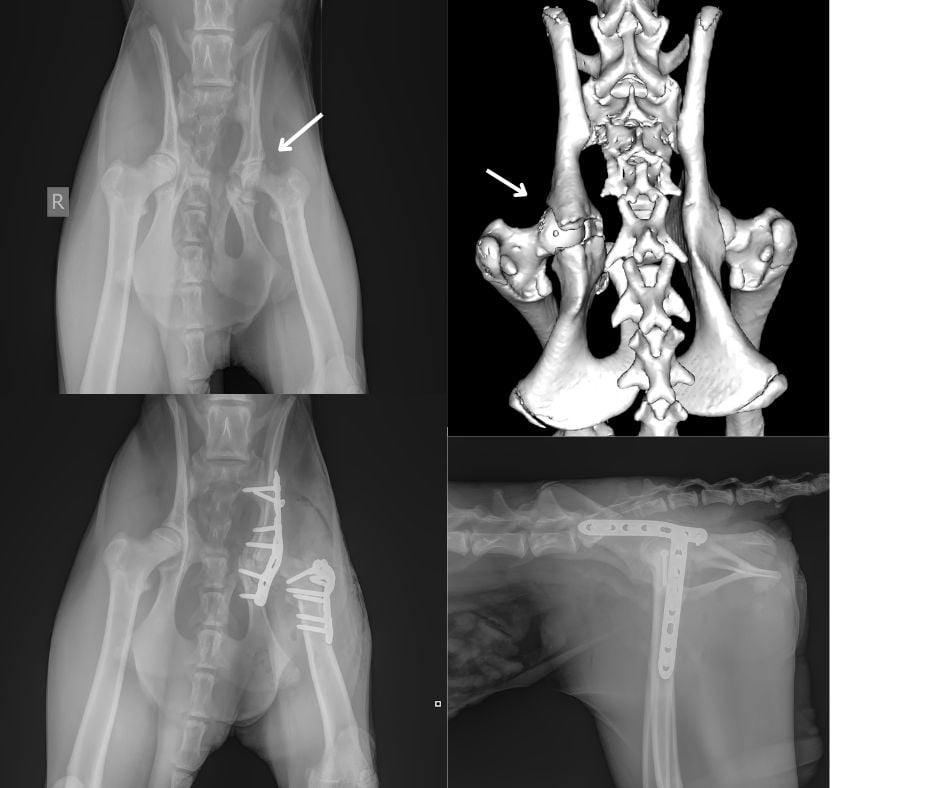

Cheeta Maisha begon plotseling ernstig mank te lopen en gebruikte haar linker achterpoot helemaal niet meer. In het park werd al snel duidelijk dat er iets goed mis was, en daarom heeft de dierenarts van de Beekse Bergen Fokko Klip Maisha laten slapen om haar achterbeen te kunnen onderzoeken en dan ook röntgenopnamen te maken. De röntgenopnamen werden aan de SDU-radiologen Dr. Susanne AEB Boroffka, dipl.ECVDI, PhD en Bas Wetzels (res.ECVDI) gestuurd voor interpretatie. Zij vonden bij de röntgenopnamen de sterke verdenking van een breuk in het linker heupgewricht. Zij hebben met Europees Specialist Chirurgie Edgar Scheepens (Dipl.ECVS) overlegd en samen met de dierenartsen van Beekse Bergen werd besloten haar naar de SDU te brengen voor verder onderzoek.

Eerst heeft Edgar Scheepens Maisha onder narcose al haar gewrichten onderzocht en voelde een subtiele kraken bij haar linker heupgewicht. Om de achterbenen goed te kunnen onderzoeken hebben we een uitgebreide CT-scan gemaakt. Daarmee wilden we niet alleen goed kijken naar het bekken, maar ook andere mogelijke verwondingen of bijzonderheden uitsluiten, zoals schade aan de rug, heup of organen (en natuurlijk om prachtige CT-beelden van een Cheeta te krijgen). Gelukkig bleek dat verder alles in orde was maar de bekkenbreuk was wel fors.

De breuk in haar heupkom (acetabulum) was waarschijnlijk al zo’n 10 dagen oud en daardoor extra lastig te herstellen. Er was al wat botweefsel gaan vormen op de verkeerde plekken, waardoor het lastiger werd om alles goed terug te zetten.

Toch is het Europees specialist chirurgie Edgar Scheepens (dipl.ECVS), met assistentie van Europees specialist chirurgie Prof. Björn Meij en Europees specialist chirurgie Nicolien van Klaveren(dipl.ECVS) gelukt om Maisha succesvol te opereren. De breuk is zo goed mogelijk hersteld met een metalen plaat en meerdere schroeven om het gewricht weer stabiel te krijgen.